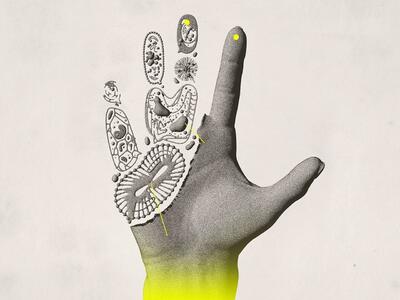

بافت بدن

پروتئین بعد از هضم شدن به واحدهای سازندهی خود یعنی اسید آمینه تجزیه میشود. اسید آمینه به عملکرد و رشد بافتهای بدن کمک کرده و از سلامت عضلات، استخوانها، پوست، مو و ناخن محافظت میکند

فتق نافی چیست؟

رکنا: فتق نافی یک وضعیت شایع است که به بیرون زدگی بافت یا اعضای داخلی بدن از طریق ناحیه ضعیف دیواره شکم اطراف ناف گفته میشود. این مشکل معمولاً در نوزادان و کودکان دیده میشود، اما در بزرگسالان نیز ممکن است رخ دهد و در بسیاری از موارد نیاز به درمان جراحی پیدا میکند.

بیماریهای خودایمنی زمانی ایجاد میشوند که سیستم ایمنی بدن که قرار است با مهاجمان بیرونی مبارزه کند، به اشتباه به بافتهای سالم خود بدن حملهور میشود. این حملات اشتباهی میتوانند التهاب، آسیب و اختلال در عملکرد انواع ارگانها و سیستمها ایجاد کنند.